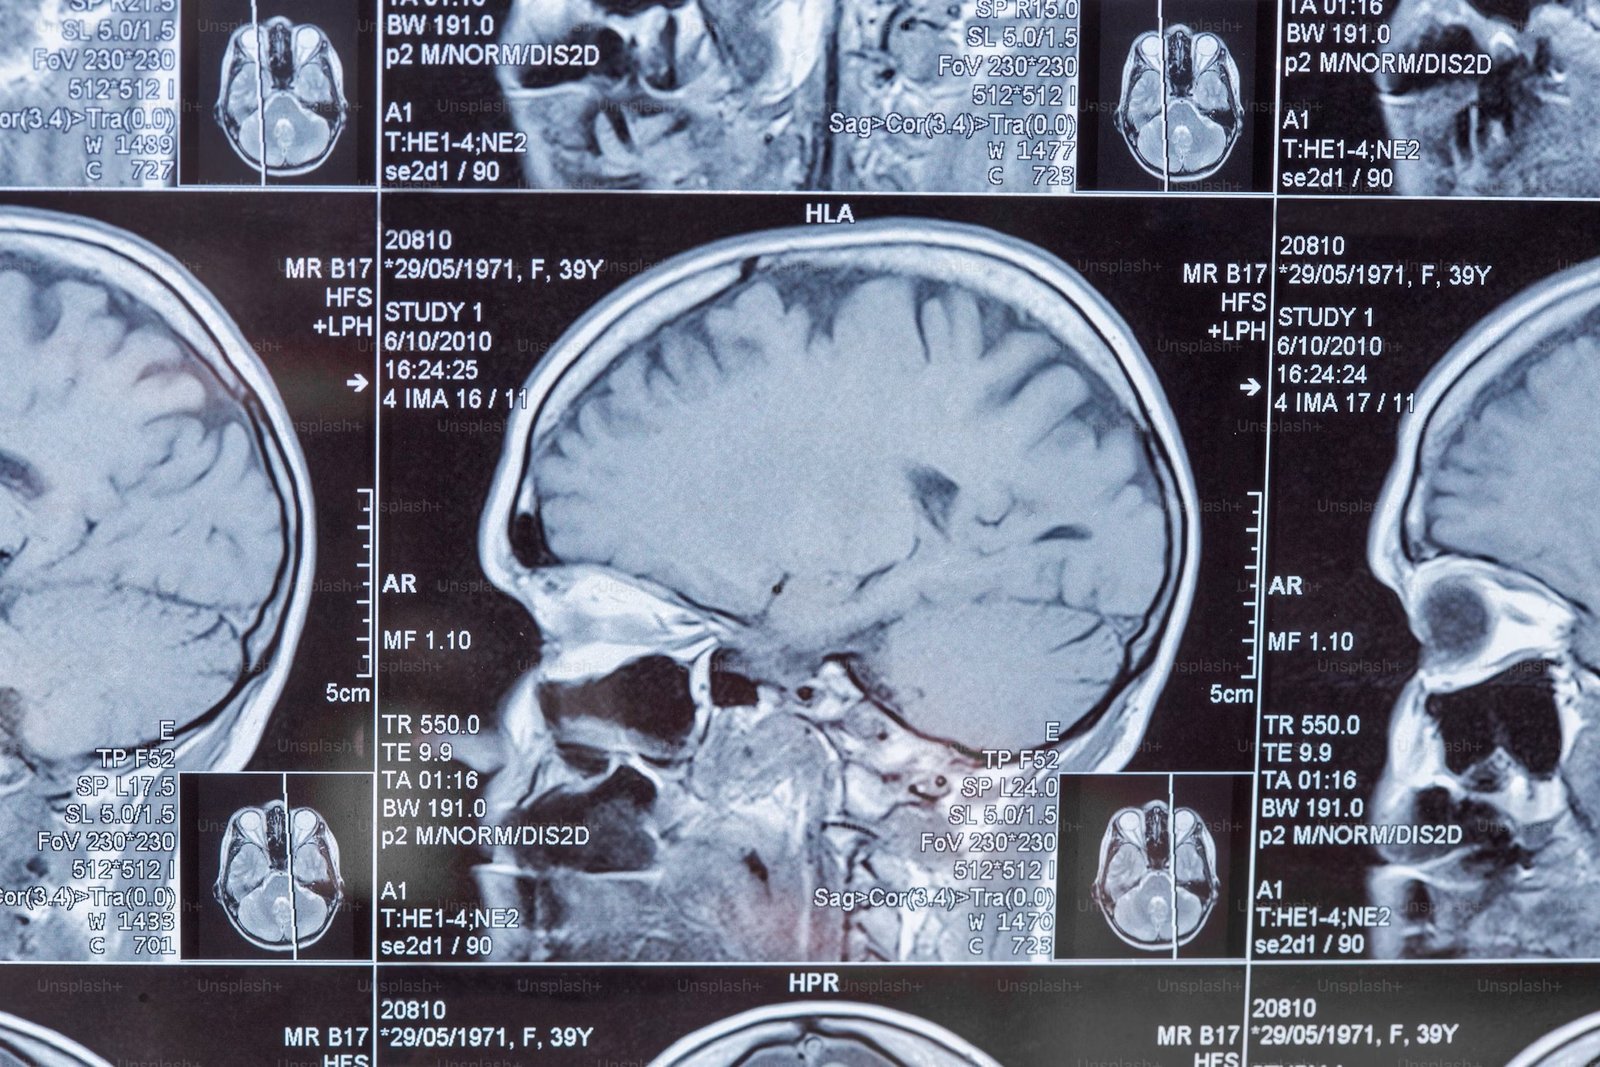

Gracias a estudios de neuroimagen (por ejemplo, resonancia magnética funcional), sabemos que los cerebros de las personas transgénero y cisgénero difieren entre sí. En estas imágenes, se analizan estructuras como el cuerpo calloso, que conecta los dos hemisferios del cerebro, el hipotálamo, una pequeña región que desempeña un papel importante en la regulación hormonal, la corteza cerebral, que contiene áreas responsables de la percepción del cuerpo y la propiocepción, y la amígdala, que participa en el procesamiento de las emociones y la respuesta al estrés. Todo esto permite especular, respaldado por estudios científicos, que el desarrollo cerebral juega un papel en la formación de la identidad de género (Savic & Arver, 2011; Spack, 2013).